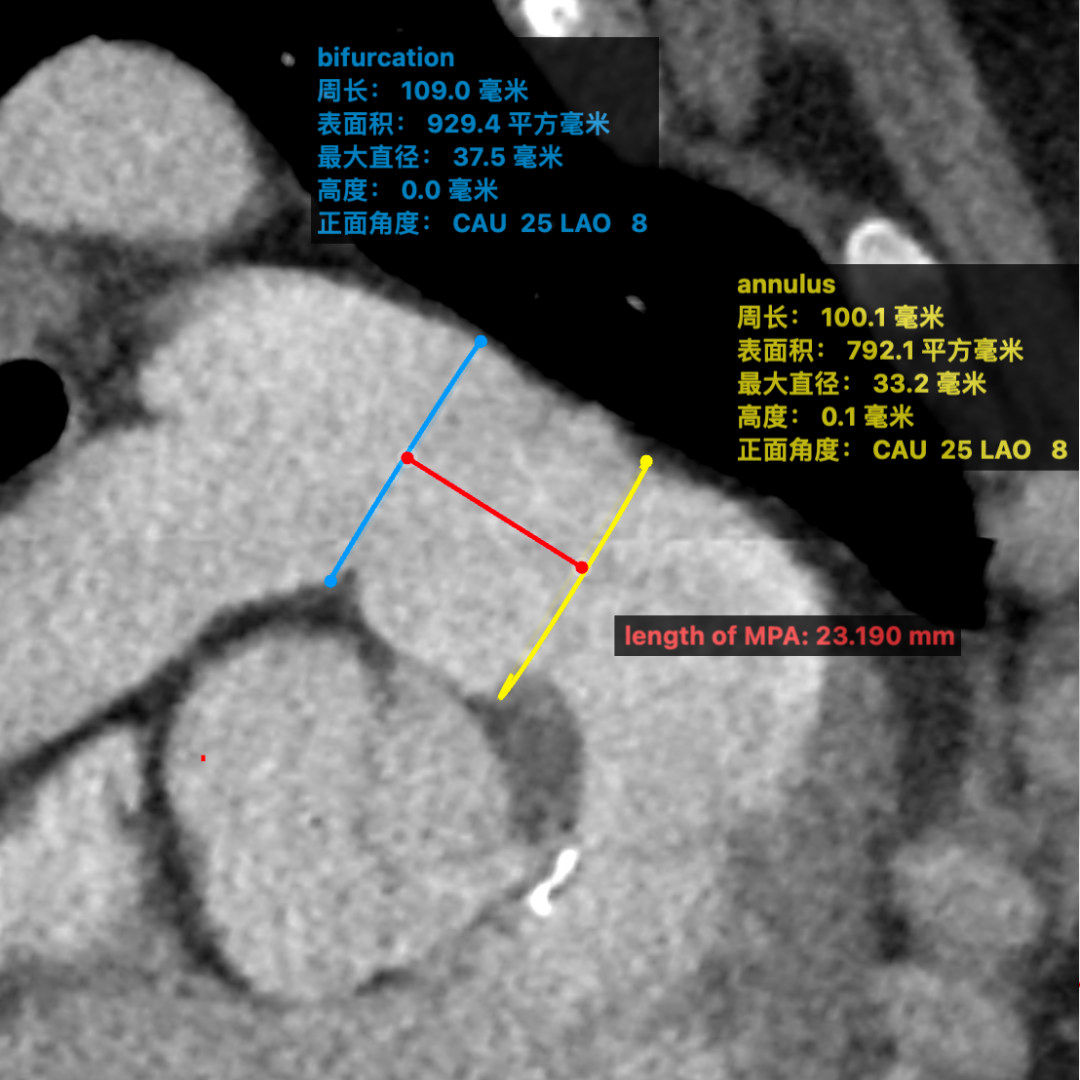

术前通过肺动脉CTA评估患者肺动脉瓣环直径为32mm、肺动脉分叉处直径为35mm、主肺动脉长度为23mm(见图一)。

图一:肺动脉瓣环直径32mm,肺动脉分叉处直径35mm,主肺动脉长度23mm